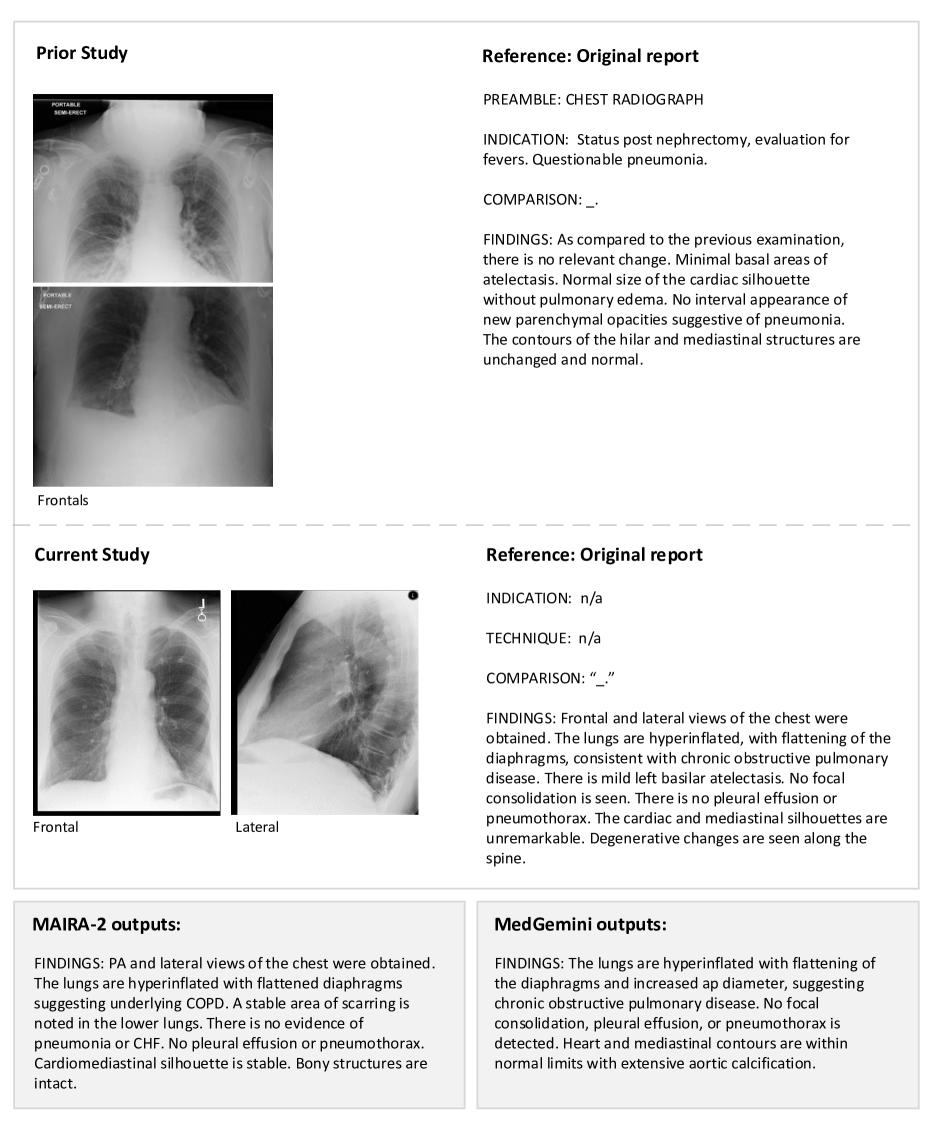

MAIRA-2 uses more comprehensive inputs than explored previously: the current frontal image, the current lateral image, the prior frontal image and prior report, as well as the Indication, Technique and Comparison sections of the current report.

Context beyond a single image plays a significant role in the contents of a radiology report, influencing both the interpretation of the image and communicative choices in the reporting itself. Hence, in this work we generate chest X-ray (CXR) reports using: the current frontal image, the current lateral image, the prior frontal image and prior report, and the Indication, Technique, and Comparison sections of the current study.

Incorporating prior and lateral images

To better understand and demonstrate the behaviour of MAIRA-2 in grounded reporting, we selected examples for qualitative review with a radiologist, shown in Figures 3 and C.

MAIRA-2 is designed and trained to handle both grounded or non-grounded report generation. Table 5 shows its performance on the MIMIC-CXR test set using both RadFact and a range of commonly reported metrics outlined in Section 2.5. We compare to the closest prior state of the art, restricted to models evaluated for Findings generation, namely Med-PaLM M (Tu et al., 2024), LLaVA-Rad (Chaves et al., 2024), MedVersa (Zhou et al., 2024), and MAIRA-1 (Hyland et al., 2023). Since many of these models are not publicly available, we present their evaluation results as originally reported, noting that the test sets are slightly different. For MAIRA-1, we obtained the model generations on the MIMIC-CXR test set in order to run RadFact and CheXprompt.

With RadFact, we see again an improvement from MAIRA-1 to MAIRA-2 and its 13B variant, in agreement with other metrics. What RadFact additionally reveals is that in absolute terms, models continue to make errors, with only 55.6% of sentences generated by MAIRA-2 13B confirmed (as per the reference report) to be true. We show qualitative examples of MAIRA-2 generations on MIMIC-CXR in Section C.3.